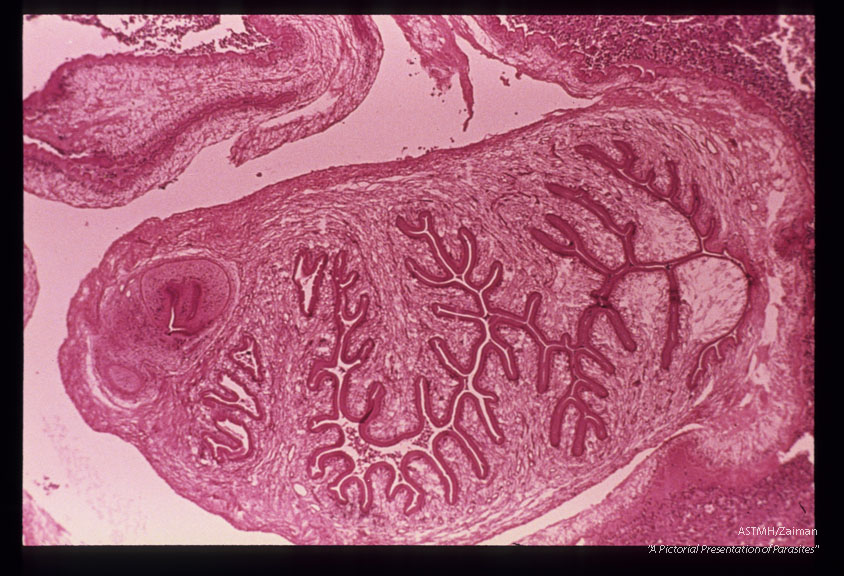

Low and high power views of cysticercus removed from buccal mucosa of patient.

Taenia solium

Description: Low and high power views of cysticercus removed from buccal mucosa of patient.